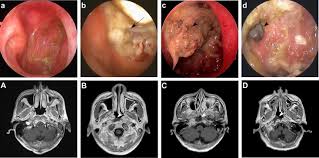

Bác sĩ sẽ kiểm tra tổng quát tình trạng vùng đầu cổ, hệ thống hạch, đặc biệt làm thăm khám bằng nội soi sẽ giúp phát hiện những tổn thương sớm, khó quan sát bằng dụng cụ khám thông thường. Hoặc khi có các dấu hiệu trên ở người có các yếu tố nguy cơ mắc bệnh ung thư vòm họng, cần đến khám bác sĩ chuyên khoa tai mũi họng để nội soi vòm họng kiểm tra phát hiện sớm đồng thời khám bác sĩ chuyên khoa ung thư để được tư vấn về chẩn đoán và điều trị.